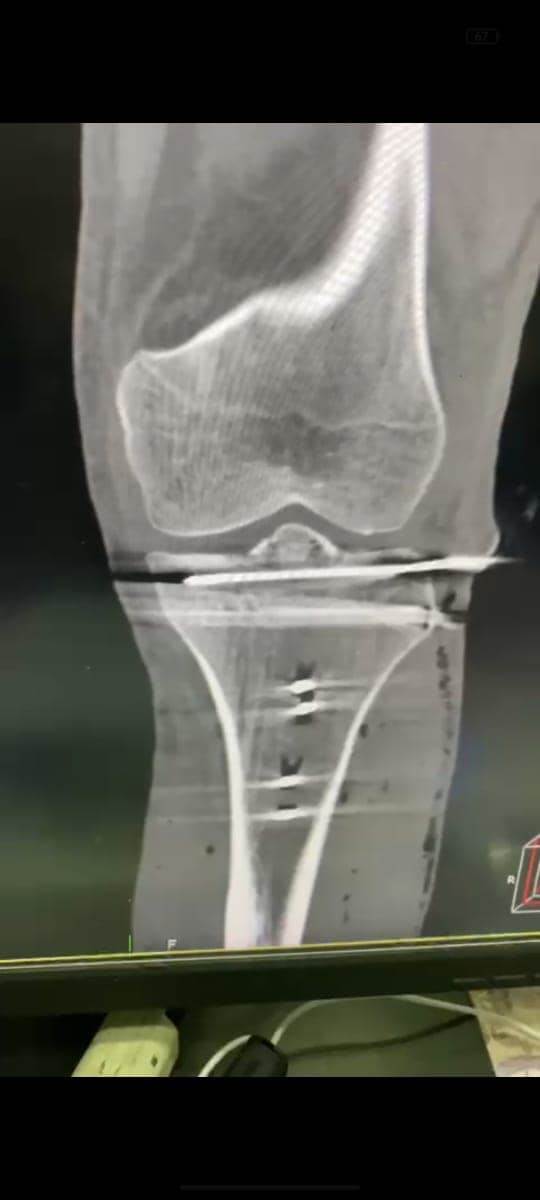

مشيرًا الى أن ذلك النوع من الكسور يكون قريبًا جدًا من الأعصاب والأوعية الدموية الرئيسية للساق والتي توجد خلف مفصل الركبة.. حيث تم الوصول الى الكسر وإعادة بناء سطح المفصل وتثبيته باستخدام شريحة ومسامير وأسلاك معدنية باستخدام جرح ٧ سنتيمترات خلف الركبة واستخدام مسامير جانبية مجوفة بدون فتح لتثبيت الجزء الخارجى من سطح المفصل، وتم الاطمئنان على الأوعية الدموية قبل إفاقة المريض، وبعد تمام الإفاقة.. تم الاطمئنان على الأعصاب والأوعية للمريض.

وأضاف أنه نظرًا لقرب هذا الكسر من سطح المفصل تم عمل أشعة مقطعية بعد الجراحة للتأكد من جودة بناء المفصل وعدم وجود أى بروز للمسامير داخل المفصل، وجارٍ تحضير المريض لعمل رنين مغناطيسى لتحديد الأربطة الداخلية والخارجية للركبة التي ستحتاج لإعادة بناء بالمنظار.